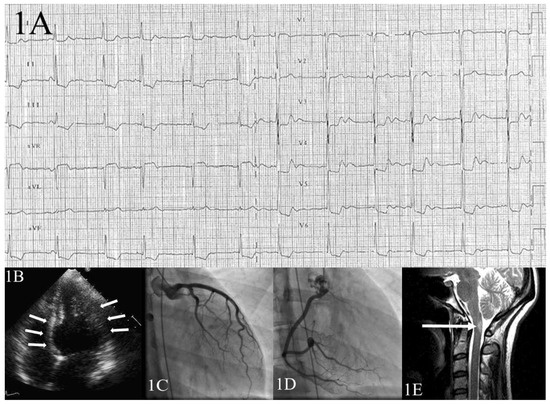

Basal Tako-Tsubo Cardiomyopathy

by Mattia Cattaneo, Alessandra Pia Porretta, Carlo Cereda, Marco Moccetti, Claudio Gobbi, Elena Pasotti, Daniel Sürder, Claudio Städler and Augusto Gallino

Tako-Tsubo cardiomyopathy (TTC) is an infrequent, mostly stress-related transient cardio myopathy, which mainly affects postmenopausal women. Inverted or basal TTC (B-TTC) episodes are rarer. Our case illustrates a rare example of B-TTC in a 30-year-old woman with an acute multiple sclerosis relapse as [...] Read more.

Tako-Tsubo cardiomyopathy (TTC) is an infrequent, mostly stress-related transient cardio myopathy, which mainly affects postmenopausal women. Inverted or basal TTC (B-TTC) episodes are rarer. Our case illustrates a rare example of B-TTC in a 30-year-old woman with an acute multiple sclerosis relapse as the associated stressor, possibly providing a hypothetical pathological substrate for this TTC episode. This uncommon case suggests that both factors of young age or neurological events may affect TTC pattern during one episode. Moreover, this case raises the question as to whether researchers on T TC should adopt a new perspective, embracing cardiovascular as well as neuroanatomical and -functional features. Full article

Figure 1